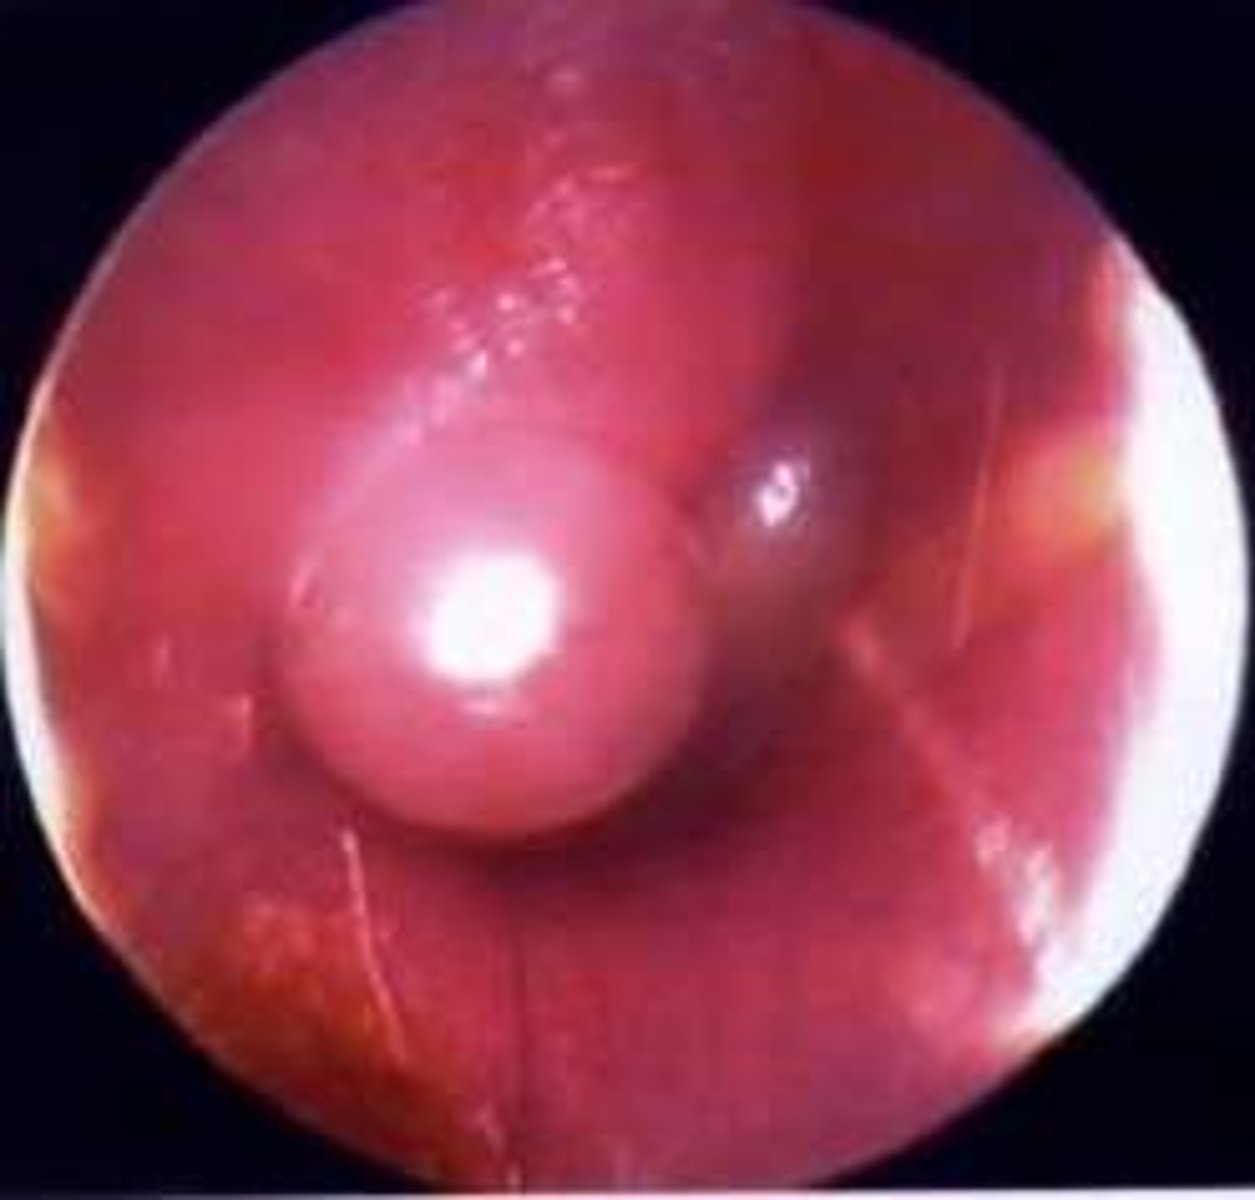

Acute otitis media

INFECTION of middle ear

TM bulging

Pain/pulling ear

Conductive HL dt purulent material

Erythema

<p>INFECTION of middle ear</p><p>TM bulging</p><p>Pain/pulling ear</p><p>Conductive HL dt purulent material</p><p>Erythema</p>